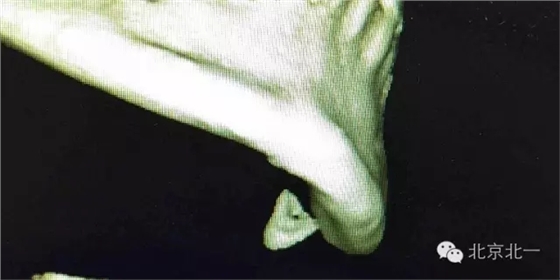

圖四:CBCT重建不同視覺看牙根位置